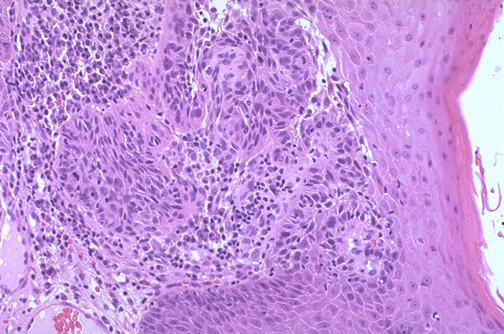

| A squamous cell carcinoma is seen here at medium power. The neoplastic cells extend downward into the dermis. Note the pleomorphism of the cells, and there is little keratinization. Compare with the normal skin at the right. An intense inflammatory infiltrate is present. |